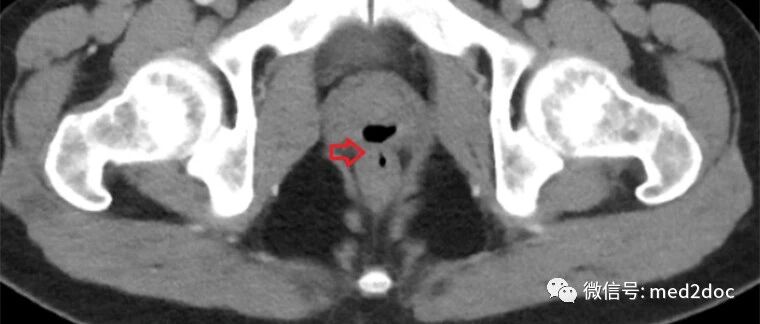

诺西那生钠(Spinraza)是一种反义寡核苷酸,可改变SMN2基因的剪接,增加全功能性SMN蛋白的生产,属于一种基因疗法药物。诺西那生钠注射液通过鞘内注射给药,可以直接将药物输送到脊髓周围的脑脊液中,从而改善运动功能、提高生存率,改变SMA的疾病进程,该药物在2018年11月颁布的2018年国际盖伦奖(2018InternationalPrixGalien)中荣获"最佳生物技术产品"的荣誉。